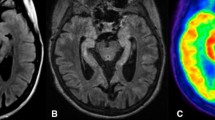

18F-FOL and 11C-PBR28 radioligands are able to detect fDTH-EAE lesions, but only 18F-FOL can differentiate between acute and chronic lesions

Both 18F-FOL and 11C-PBR28 radiotracers were able to detect the inflammatory fDTH-EAE lesions (Figs. 2, 3, and 4). In vivo PET/CT imaging with 18F-FOL and 11C-PBR28 showed focal uptake in the induced brain hemisphere, which was co-localized with the MRI-depicted lesion. Tracer kinetics, i.e., time-activity curves (TACs), revealed a significant difference between the lesion and contralateral hemispheres in all studied groups (P < 0.0001, Fig. 4a). In the chronic phase, 18F-FOL showed significantly higher uptake than 11C-PBR28 (P = 0.016, Fig. 4a, b) at the lesion site, but no other differences between the tracers or the acute and chronic phases were observed. A significant correlation was observed between in vivo and ex vivo measurements of both 18F-FOL and 11C-PBR28 tracers (18F-FOL: R = 0.95, P = 0.0004, 11C-PBR28: R = 0.76, P = 0.037, Fig. 4c).

In vivo multimodal imaging of fDTH-EAE rat brain at acute (day 14) and chronic (day 90) phases of disease development with quantitative data. a Representative coronal MRI, 18F-FOL, and 11C-PBR28 PET/CT images and corresponding time-activity curves. White arrows denote inflammatory lesions. All PET images are displayed using the same color scale. Tracer uptake in the lesion is significantly higher than that in the contralateral site. ***P < 0.001. b Quantitative PET data presented as SUV ratios reveal significant differences between tracers in the chronic phase, but not in the acute phase. *P < 0.05. c Comparison of in vivo and ex vivo PET data. SUV ratio = SUVmax(lesion)/SUVmean(contralateral). R2 is Spearman’s correlation coefficient. Error bars denote standard deviation

Both 18F-FOL and 11C-PBR28 PET radioligands were able to visualize acute and chronic focal EAE inflammatory lesions. However, 18F-FOL was able to demonstrate differences between small acute lesions and large chronic progressive lesions, differences that 11C-PBR28 was unable to detect in EAE (Figs. 2 and 3). In addition, 18F-FOL showed a lower background signal than 11C-PBR28 (Figs. 2 and 3). This is especially beneficial, as current activated macrophage and microglia detecting TSPO tracers, including 11C-PBR28, still have relatively high background signals when used to image neuroinflammation [14, 16, 17]. Hence, 18F-FOL shows desirable attributes for imaging of inflammatory CNS lesions. However, because the spatial resolution and sensitivity of ex vivo digital autoradiography are much better than that of in vivo PET imaging, we consider ex vivo digital autoradiography to be the most reliable method for evaluating new molecular imaging tracers in rodent models. In vivo 18F-FOL PET/CT showed a moderate ability to visualize changes occurring in inflammatory activity when fDTH-EAE lesions progressed to the chronic phase. Unfortunately, because of the smaller size of acute lesions, their detection on in vivo PET was not as optimal as with the larger chronic lesions (Table 1). The Inveon small animal PET provides a spatial resolution of approximately 1.6 mm for 18F [33]. Note, for logistical reasons, we were able to perform longitudinal PET/CT imaging only for some group B animals and we were unable to mix the 11C-PBR28/18F-FOL scan order, even though that was the original plan. In addition, in this study, we chose to determine the size of the lesion by ex vivo analysis because, due to random coil failure, not all MR images were of the same high quality.